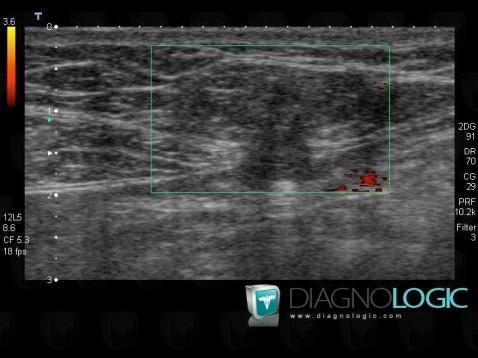

Epigastric hernia, Abdominal wall, US

Here is the specific information in the key image above:

- Diagnosis Epigastric hernia, Location(s) Abdominal wall, with gamuts Abdominal wall mass